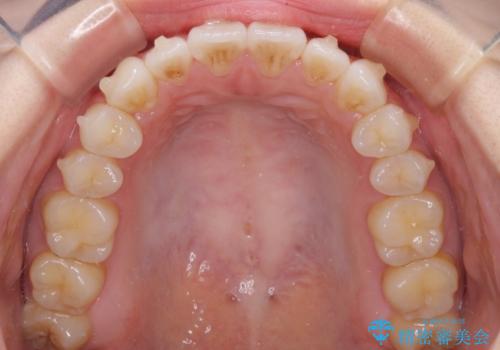

- 矯正治療の後戻りを気にして来院された患者様です。

後戻りは軽微でしたが、舌突出癖が認められ、初診時には上下前歯に舌がはまるスペースができていました。

舌突出癖の改善を行いながら、インビザライン・ライトにより矯正治療を行うこととしました。

舌突出癖の改善により上下前歯が接触するようになり、前歯でものを咬みきる必要のある食事がスムーズに行えるようになりました。